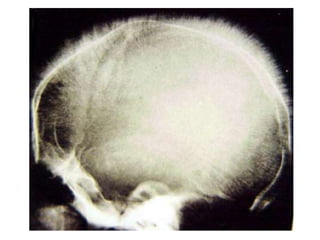

C- Rx :

• Anomalies de la voûte du crâne

• Lithiase pigmentaire

aspect en poils de brosse

5. Radiologie

 Rx crâne: Aspect en poils de brosse (état évolué)